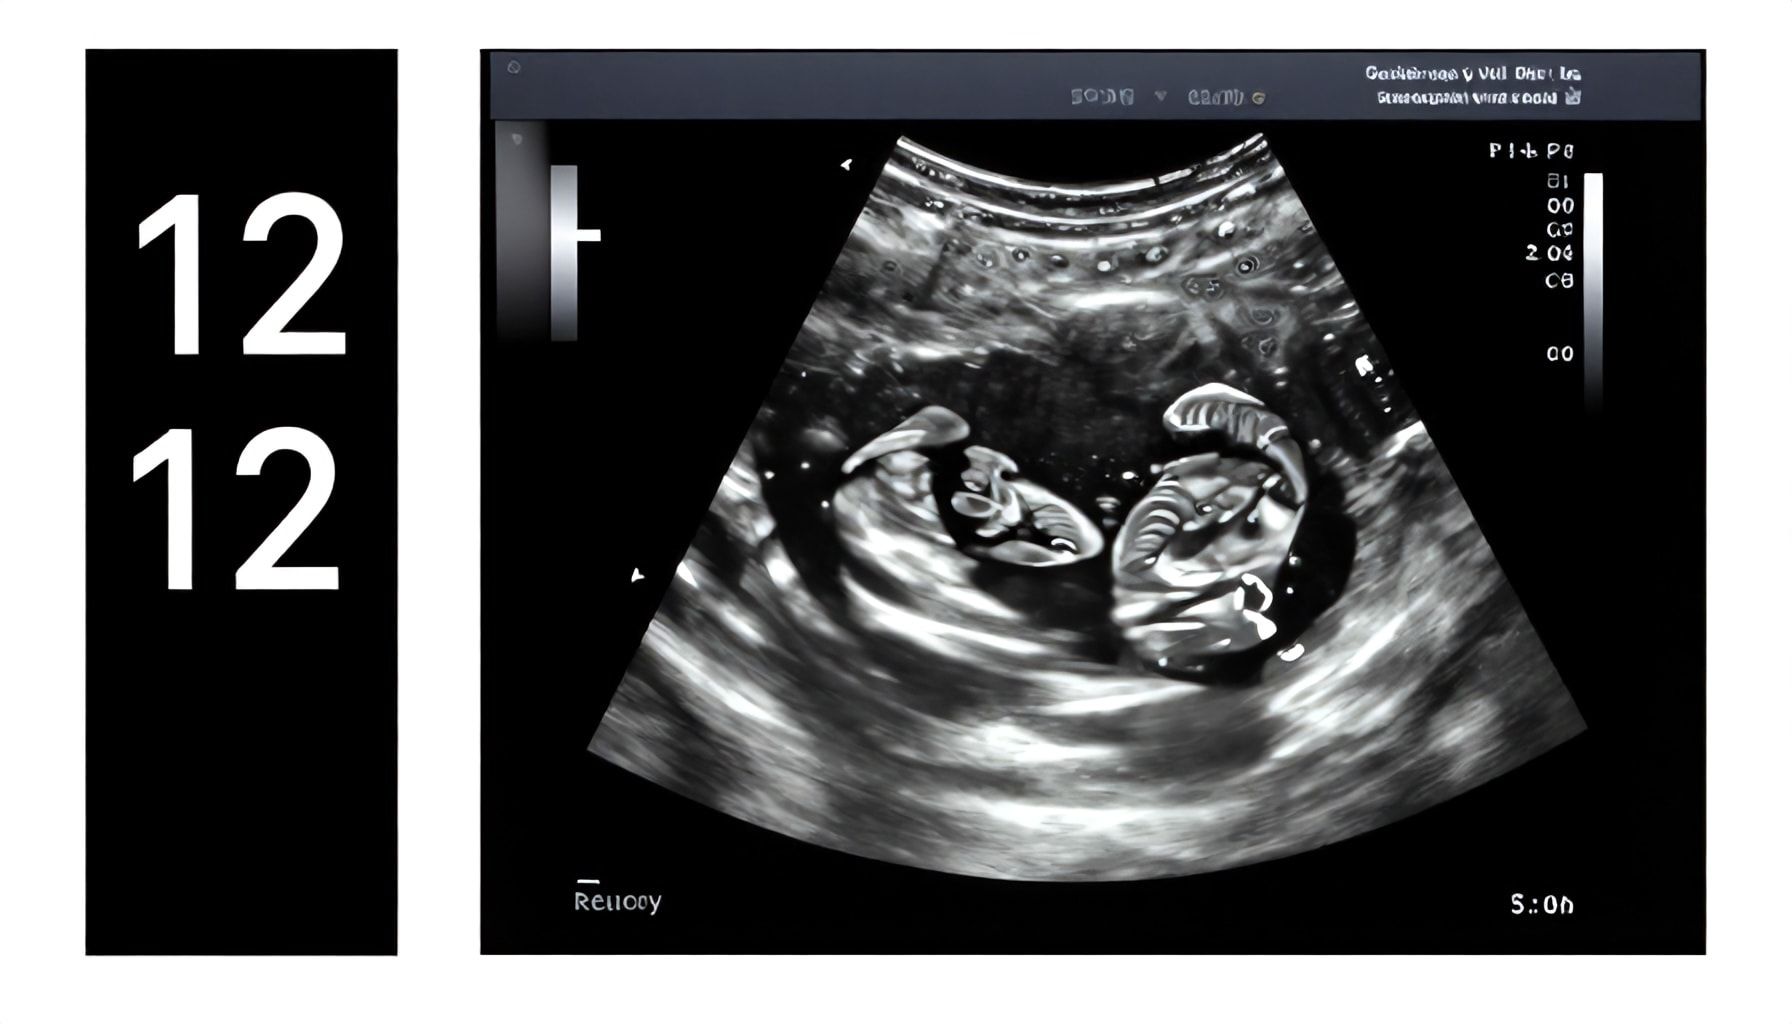

The 12-week ultrasound is one of the most fascinating milestones in your pregnancy journey. I’ve done thousands of these scans over the years, and every time, I still get a kick out of seeing how much progress your baby has made in just three months. Here are the five key things you’ll likely spot during this scan—and why they matter.

- Heartbeat: By now, your baby’s heart is pumping around 120-160 beats per minute—nearly twice as fast as yours. I’ve seen parents gasp when they hear it for the first time. It’s a full-on drum solo in there.

- Movement: Tiny, jerky motions. Your baby’s limbs are starting to move, though you won’t feel it yet. On the screen, you might catch a little arm or leg flailing. It’s like watching a tiny, very determined acrobat.

- Head-to-body ratio: At this stage, your baby’s head makes up about half their length. It’s all brain growth, folks. Their body will catch up soon, but for now, they look like a little alien with a giant noggin.

- Nuchal translucency: This is the measurement of fluid at the back of your baby’s neck. It’s part of screening for chromosomal conditions. I always tell parents: Don’t stress the numbers—this is just data, not a diagnosis.

- Yolk sac visibility: Early on, the yolk sac is a critical lifeline. By 12 weeks, it’s shrinking as the placenta takes over. If it’s still visible, no big deal—just means your baby’s development is right on schedule.